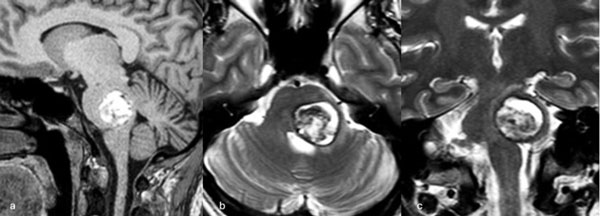

Figura 3. RM preoperatoria de encéfalo. Se evidencia una lesión única intraaxial centrada en puente y pedúnculo cerebeloso derecho, sugerente de un cavernoma roto. A, B y C) Imágenes ponderadas en T2 en cortes sagital, axial y coronal, respectivamente, donde se observa un importante hiperintensidad perilesional, sugerente de edema.

Figura 6. RM preoperatoria de encéfalo. Se evidencia una lesión única intraaxial localizada en el puente y pedúnculo cerebeloso medio izquierdo, hiperintensa en T1 y con un anillo hipointenso en T2, característica de una malformación cavernomatosa con sangrado reciente. A) Imagen ponderada en T1 en corte sagital. B y C) Imágenes ponderadas en T2 en cortes axial y coronal, respectivamente.